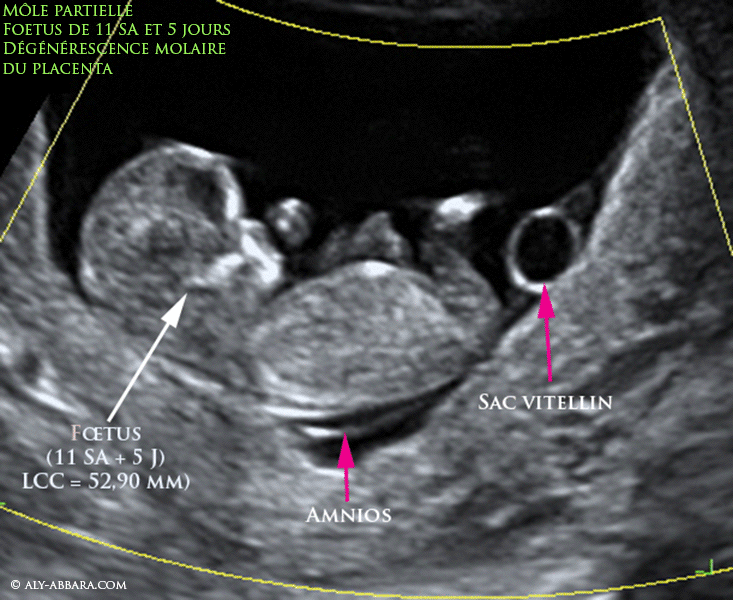

Grossesse molaire partielle - Foetus vivant de 11 SA et 5 jours, morphologiquement normale, présence d'une cavité amniotique et d'un sac vitellin, mais placenta en état d'une dégénréscence molaire polyvésiculaire

Grossesse molaire partielle (môle embryonnée) - Fœtus vivant de 11 SA et 5 jours, morphologiquement normale, présence d'une cavité amniotique et d'un sac vitellin, mais placenta en état d'une dégénérescence molaire polyvésiculaire

• Images échographiques et macroscopiques d'une grossesse molaire de 11 SA